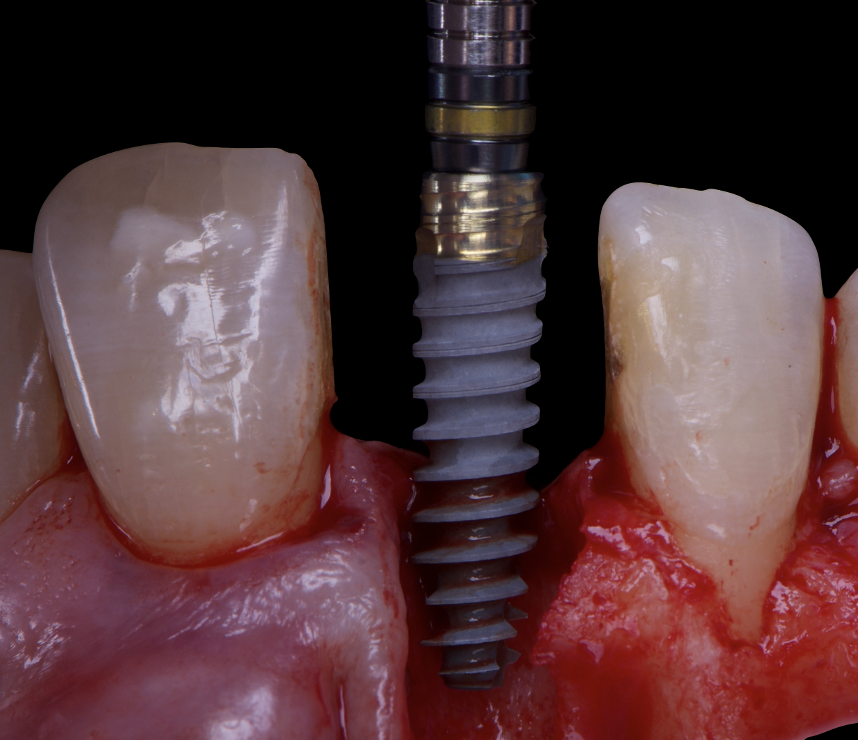

The surgical protocol began with the atraumatic extraction of tooth 1.1 to preserve as much of the alveolar socket as possible. Immediately following extraction, an N1 implant was placed into the socket using a guided surgical approach to ensure ideal three-dimensional positioning. The “one abutment one time” technique was applied to minimize soft tissue manipulation during the healing phase, which is particularly important in esthetic areas.

Given the significant buccal defect, guided bone regeneration (GBR) was performed simultaneously. A mixture of autologous bone and creos™ xenogain™ was applied to the defect and covered with a resorbable creos™ membrane to restore ridge width and support the buccal contour. In addition, a connective tissue graft was harvested and placed in the vestibular region to increase the thickness of keratinized mucosa. This combined approach addressed both hard and soft tissue deficiencies, providing the biological foundation for a stable and esthetic outcome.

On the same day as the surgery, an immediate-load provisional crown was delivered. This restoration was fabricated in acrylic resin and screw-retained on the implant, following the “one abutment one time” principle. The provisional crown was carefully adjusted to avoid occlusal loading while supporting the peri-implant soft tissue architecture during the healing phase.